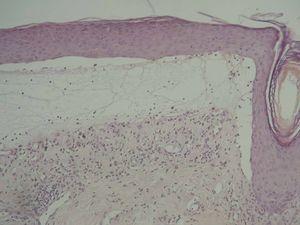

La biopsia del borde de una ampolla tensa mostró una imagen característica de penfigoide ampolloso (fig. 5). Se veía la formación de una ampolla subepidérmica con un infiltrado compuesto por linfocitos y eosinófilos. No existían cambios liquenoides en la epidermis sobre la ampolla. El estudio mediante inmunofluorescencia directa del área perilesional de la ampolla reveló un depósito lineal de C3 (fig. 6) y no se detectaron depósitos de IgG, IgM ni IgA. Mediante inmunohistoquímica se tiñó el colágeno IV (situado en la lámina densa de la membrana basal), y se vio que la separación se encontraba por encima del colágeno IV (fig. 7).

Fig. 5.—Biopsia del borde de una ampolla tensa, que muestra una imagen característica de penfigoide ampolloso.